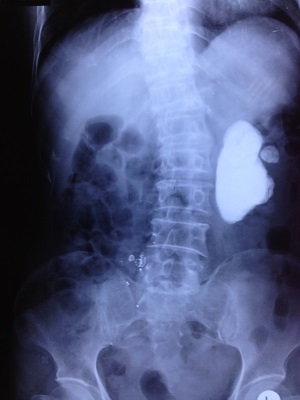

Các loại sỏi tiết niệu và sỏi thận đã được phẫu thuật tại Bệnh viện Đa khoa Ninh Bình